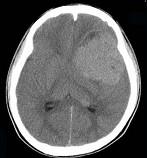

男,15岁,进行性头痛1年余,CT检查如图所示,最可能的诊断为()A.脑膜瘤B.脑血管畸形C.转移瘤D.淋巴瘤E.胶质母细胞瘤

问题 男,15岁,进行性头痛1年余,CT检查如图所示,最可能的诊断为()

选项 A.脑膜瘤 B.脑血管畸形 C.转移瘤 D.淋巴瘤 E.胶质母细胞瘤

答案 E